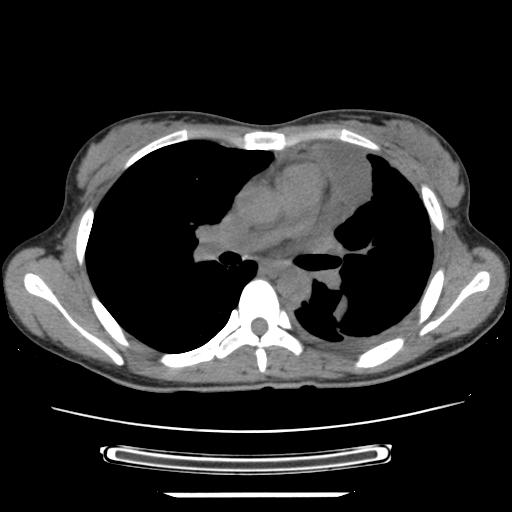

标题: CT21561:外院胸片提示胸腔积液,行CT检查。 [打印本页]

女,29岁,胸部不适,在外院胸片提示胸腔积液,到我院ct检查。

纵膈窗